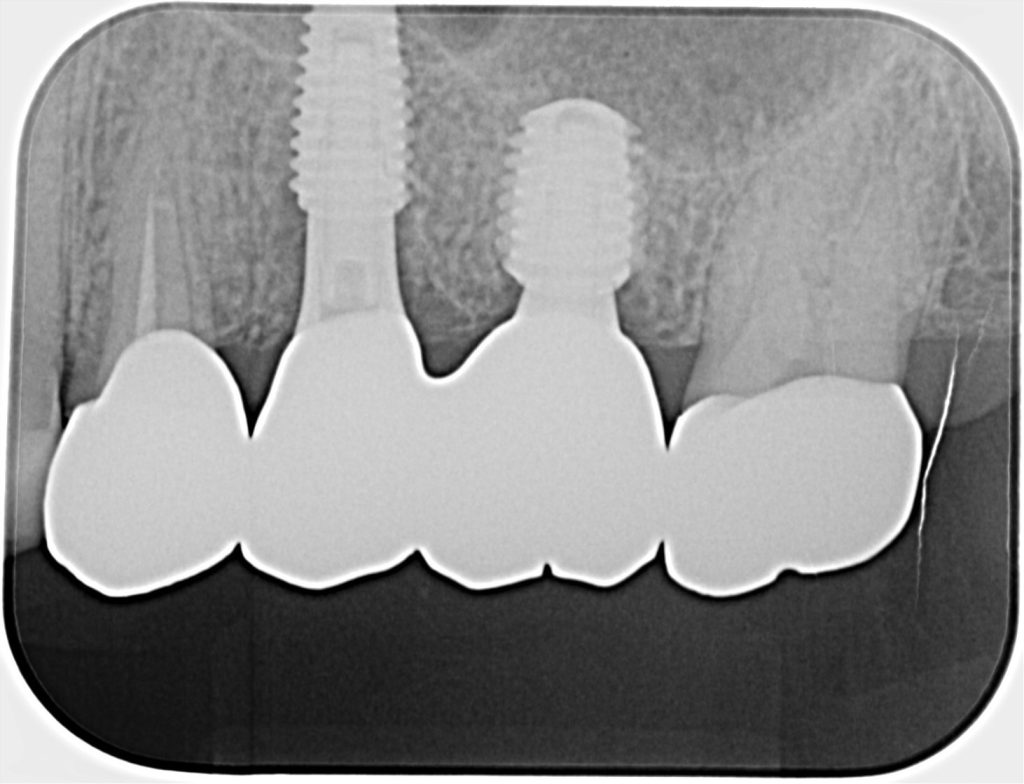

50代、男性、左上に違和感があることを主訴に来院され、インプラント治療を行いました。

| 診断結果 | 左上5番歯根破折 |

| 治療内容 | 抜歯即時インプラント |

| 治療期間 | 10週間 |

| 治療費用 | ¥946,000(税込) |